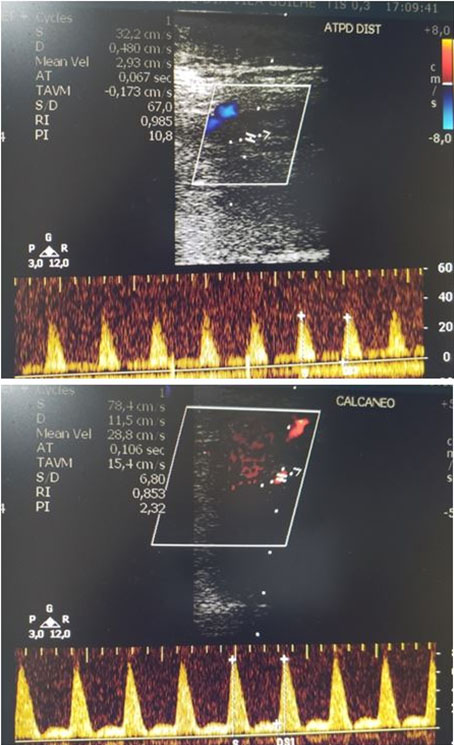

Two arterial Doppler US examinations were performed during PBM treatment, in addition to the preliminary diagnostic examination. The first of which was performed after about three months of treatment and the second after six months.

In the arterial Doppler US exam after three months of treatment, the presence of distal flow was observed in the topography of the posterior tibial artery “Tardus Parvus,” compatible with postocclusive flow.

In the six-month arterial Doppler examination, a more prominent collateral network was observed, with flow present in the topography of the distal posterior tibial artery and in the triphasic calcaneal topography (Figure 3).

Figure 3: Doppler of the posterior tibial artery D and the calcaneus region D after six months of PBM treatment. With spectral analysis it was possible to detect a flow in the distal segment of the posterior tibial artery and plantar artery (calcaneus), both with a triphasic wave pattern.

It was observed that PBM proved to be effective for the formation of collateral circulation in the region of the lesion, initially, by the presence of postocclusive flow (Tardus Parvus) and then with normal triphasic flow detected by arterial Doppler US analysis, despite only partial healing of the lesion.